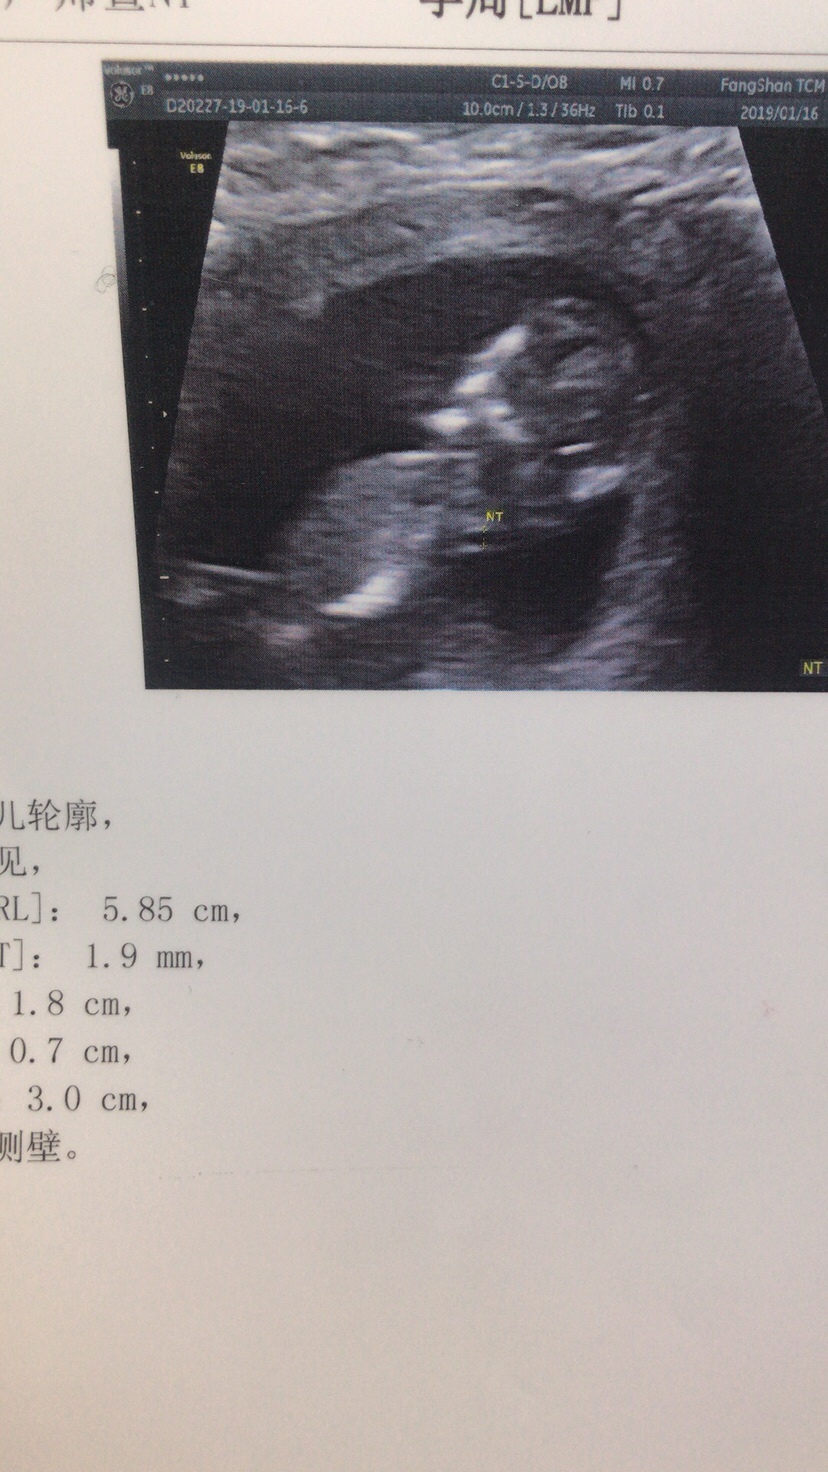

孕12周+4天

接nt顺顺利利的通过

孕9周+4天

接NT顺利通过